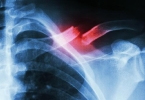

• 进行性血胸的诊断依据

进行性血胸的诊断依据

进行性血胸的诊断依据主要有胸腔引流液持续增多、血红蛋白进行性下降、影像学检查显示胸腔积液增加、生命体征不稳定、胸部外伤病史等。1、胸腔引流液持续增多进行性血胸患者胸腔闭式引流后,每小时引流量超过200毫升 ...